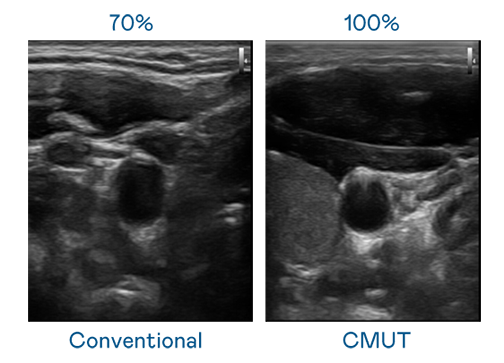

CMUT 技术是一种用电容式微机电元件来产生超音波讯号的技术。与传统 PZT 压电式技术相比,CMUT 频宽增加 30%,更宽频的超音波讯号让影像解析度大幅提升,是实现高影像品质医疗超音波扫描、促进精准医疗发展的关键技术。

大频宽带来超清晰影像

超音波影像的解析度高低,首先取决于探头能发出的讯号频宽。ag亚娱 CMUT 可提供高清晰的超音波讯号,提供高频宽、高灵敏度、影像纹理细节更高的超音波影像,协助医护人员缩短影像判读时间及利用精准的医疗影像进行诊断。